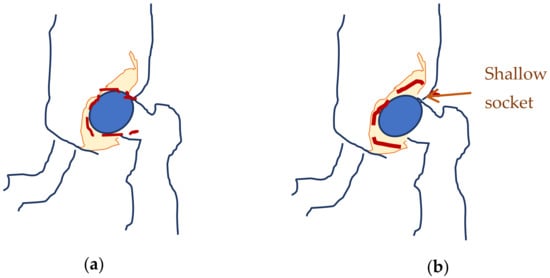

The original recording is displayed in Figure 3. As a first processing step, a color palette has been added to the original ultrasound in order to better highlight the noise and noise-free zones (Figure 4). The wavelet-based filter, as described in Section 2, is applied, and the processed image is shown in Figure 5.

We can remark, when analyzing the zoomed parts of Figure 4 and Figure 5 (the acetabulum), that in the original image speckle noise appears, strongly affecting the image. The filtering system proposed in this paper does not completely remove the speckle but brightens the image, at the same time not oversmoothing the original image. The main bone structure can be better outlined. A comparison between the same zoomed region of interest in the original image and denoising result, showing the disappearance of the speckle grains (Figure 6)—resulting thus in a smoother image where anatomical features can be better outlined.

Figure 3. Original recorded data.

Figure 4. Original data with an added color palette. A region of interest containing some speckle grains was encircled in yellow.